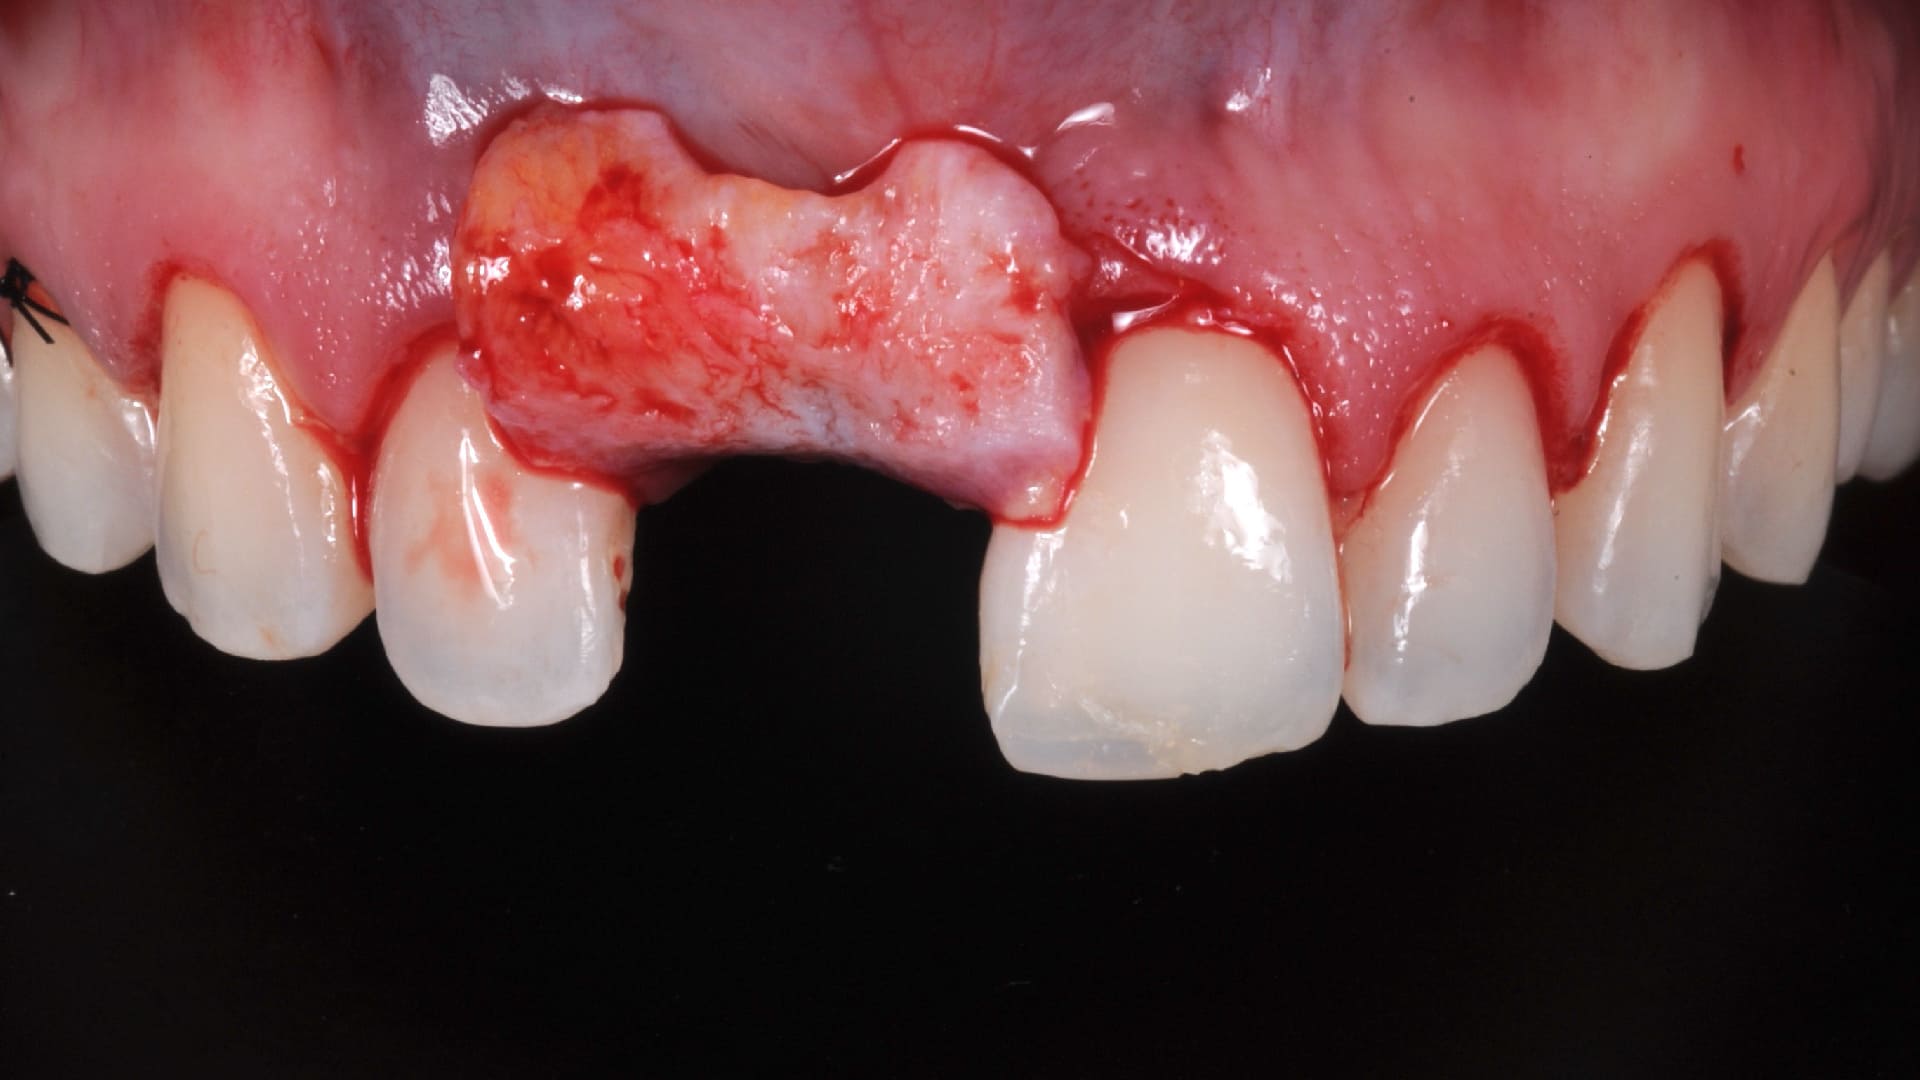

Immediate implant placement

Socket reconstruction with biomaterials and CTG

Fresh-sockets treatment Options

IP Protocols and Decision Tree at Fresh Sockets.

When, Why, and How to use the Connective Tissue Graft at.

Immediate Implants.